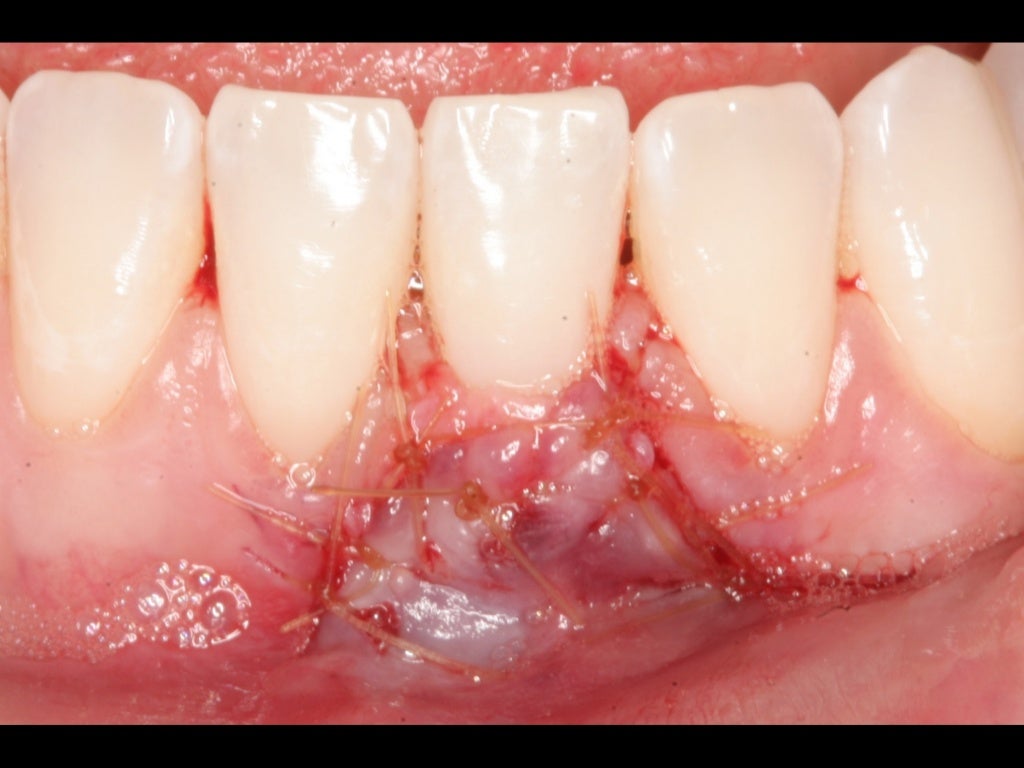

The present case report describes the novel combination of connective tissue graft (ctg) wall technique with xenograft for periodontal regeneration of extensive intrabony defects in the. Gum grafting covers exposed teeth roots and adds volume to your gum line, improving overall oral. Consequently, collagen matrices (cm) have been described as an unlimited alternative to autogenous connective tissue grafting and have been used for soft tissue augmentation.

Gum graft surgery is a dental procedure for treating thinning gums or gum recession. This technique is currently used in most soft tissue grafts performed in periodontal plastic surgery. A less invasive approach to autogenous gum grafting.

The coronally advanced flap (caf) and the use of autogenous connective tissue remains the gold standard and procedure of choice for the treatment of gingival recession at.

A less invasive approach to autogenous gum grafting. The coronally advanced flap (caf) and the use of autogenous connective tissue remains the gold standard and procedure of choice for the treatment of gingival recession at. Connective tissue grafting involves using donor tissue (nonautogenous) or soft tissue from the roof of your mouth (autogenous) to cover exposed root surfaces and rebuild your gum line.

This technique is currently used in most soft tissue grafts performed in periodontal plastic surgery. Rather than utilizing a patient’s own tissue from the palate, alloderm or allograft is used to treat areas of recession. Consequently, collagen matrices (cm) have been described as an unlimited alternative to autogenous connective tissue grafting and have been used for soft tissue augmentation.